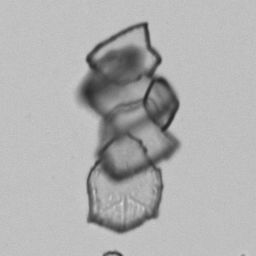

Uric acid - Irregular

Uric acid crystals occur with increased uric acid excretion or in acidic urine (pH < 5.8). Uric acid is a waste product of purine metabolism; purines are chemical compounds such as adenine and guanine (DNA components), caffeine and xanthine, and are mainly found in meat (products). The crystals can take various forms: usually diamond- or diamond-shaped plates, hexagonal plates, cylindrical structures (barrels), elongated prisms, star-shaped, spherical, needle-shaped or dumbbell-shaped crystals. They are usually yellowish to brown in color and show strong, polychromatic birefringence. They may precipitate when the urine has been kept cold prior to analysis.

The yellow discoloration of the crystals in this preparation is caused by fixation with glutaraldehyde.